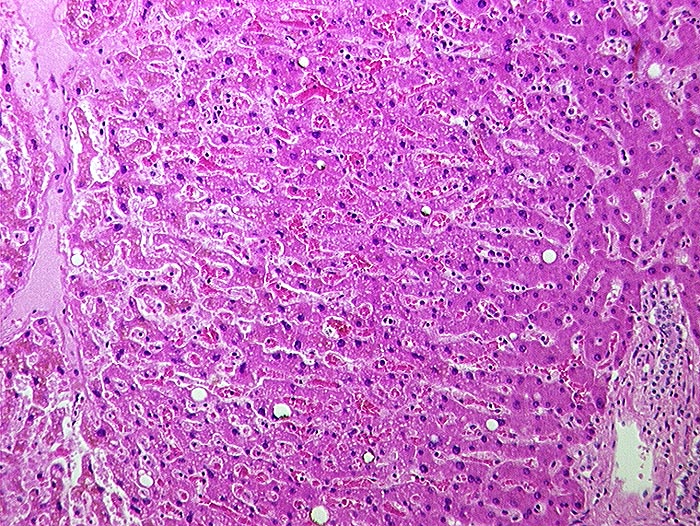

AP/ Subakute Stauung der Leber

Subakute Stauung der Leber

vaskulär / Durchblutungsstörung

Leber, Gallenwege, Pankreas

Leber

Leber HE

Pathologischer Befund